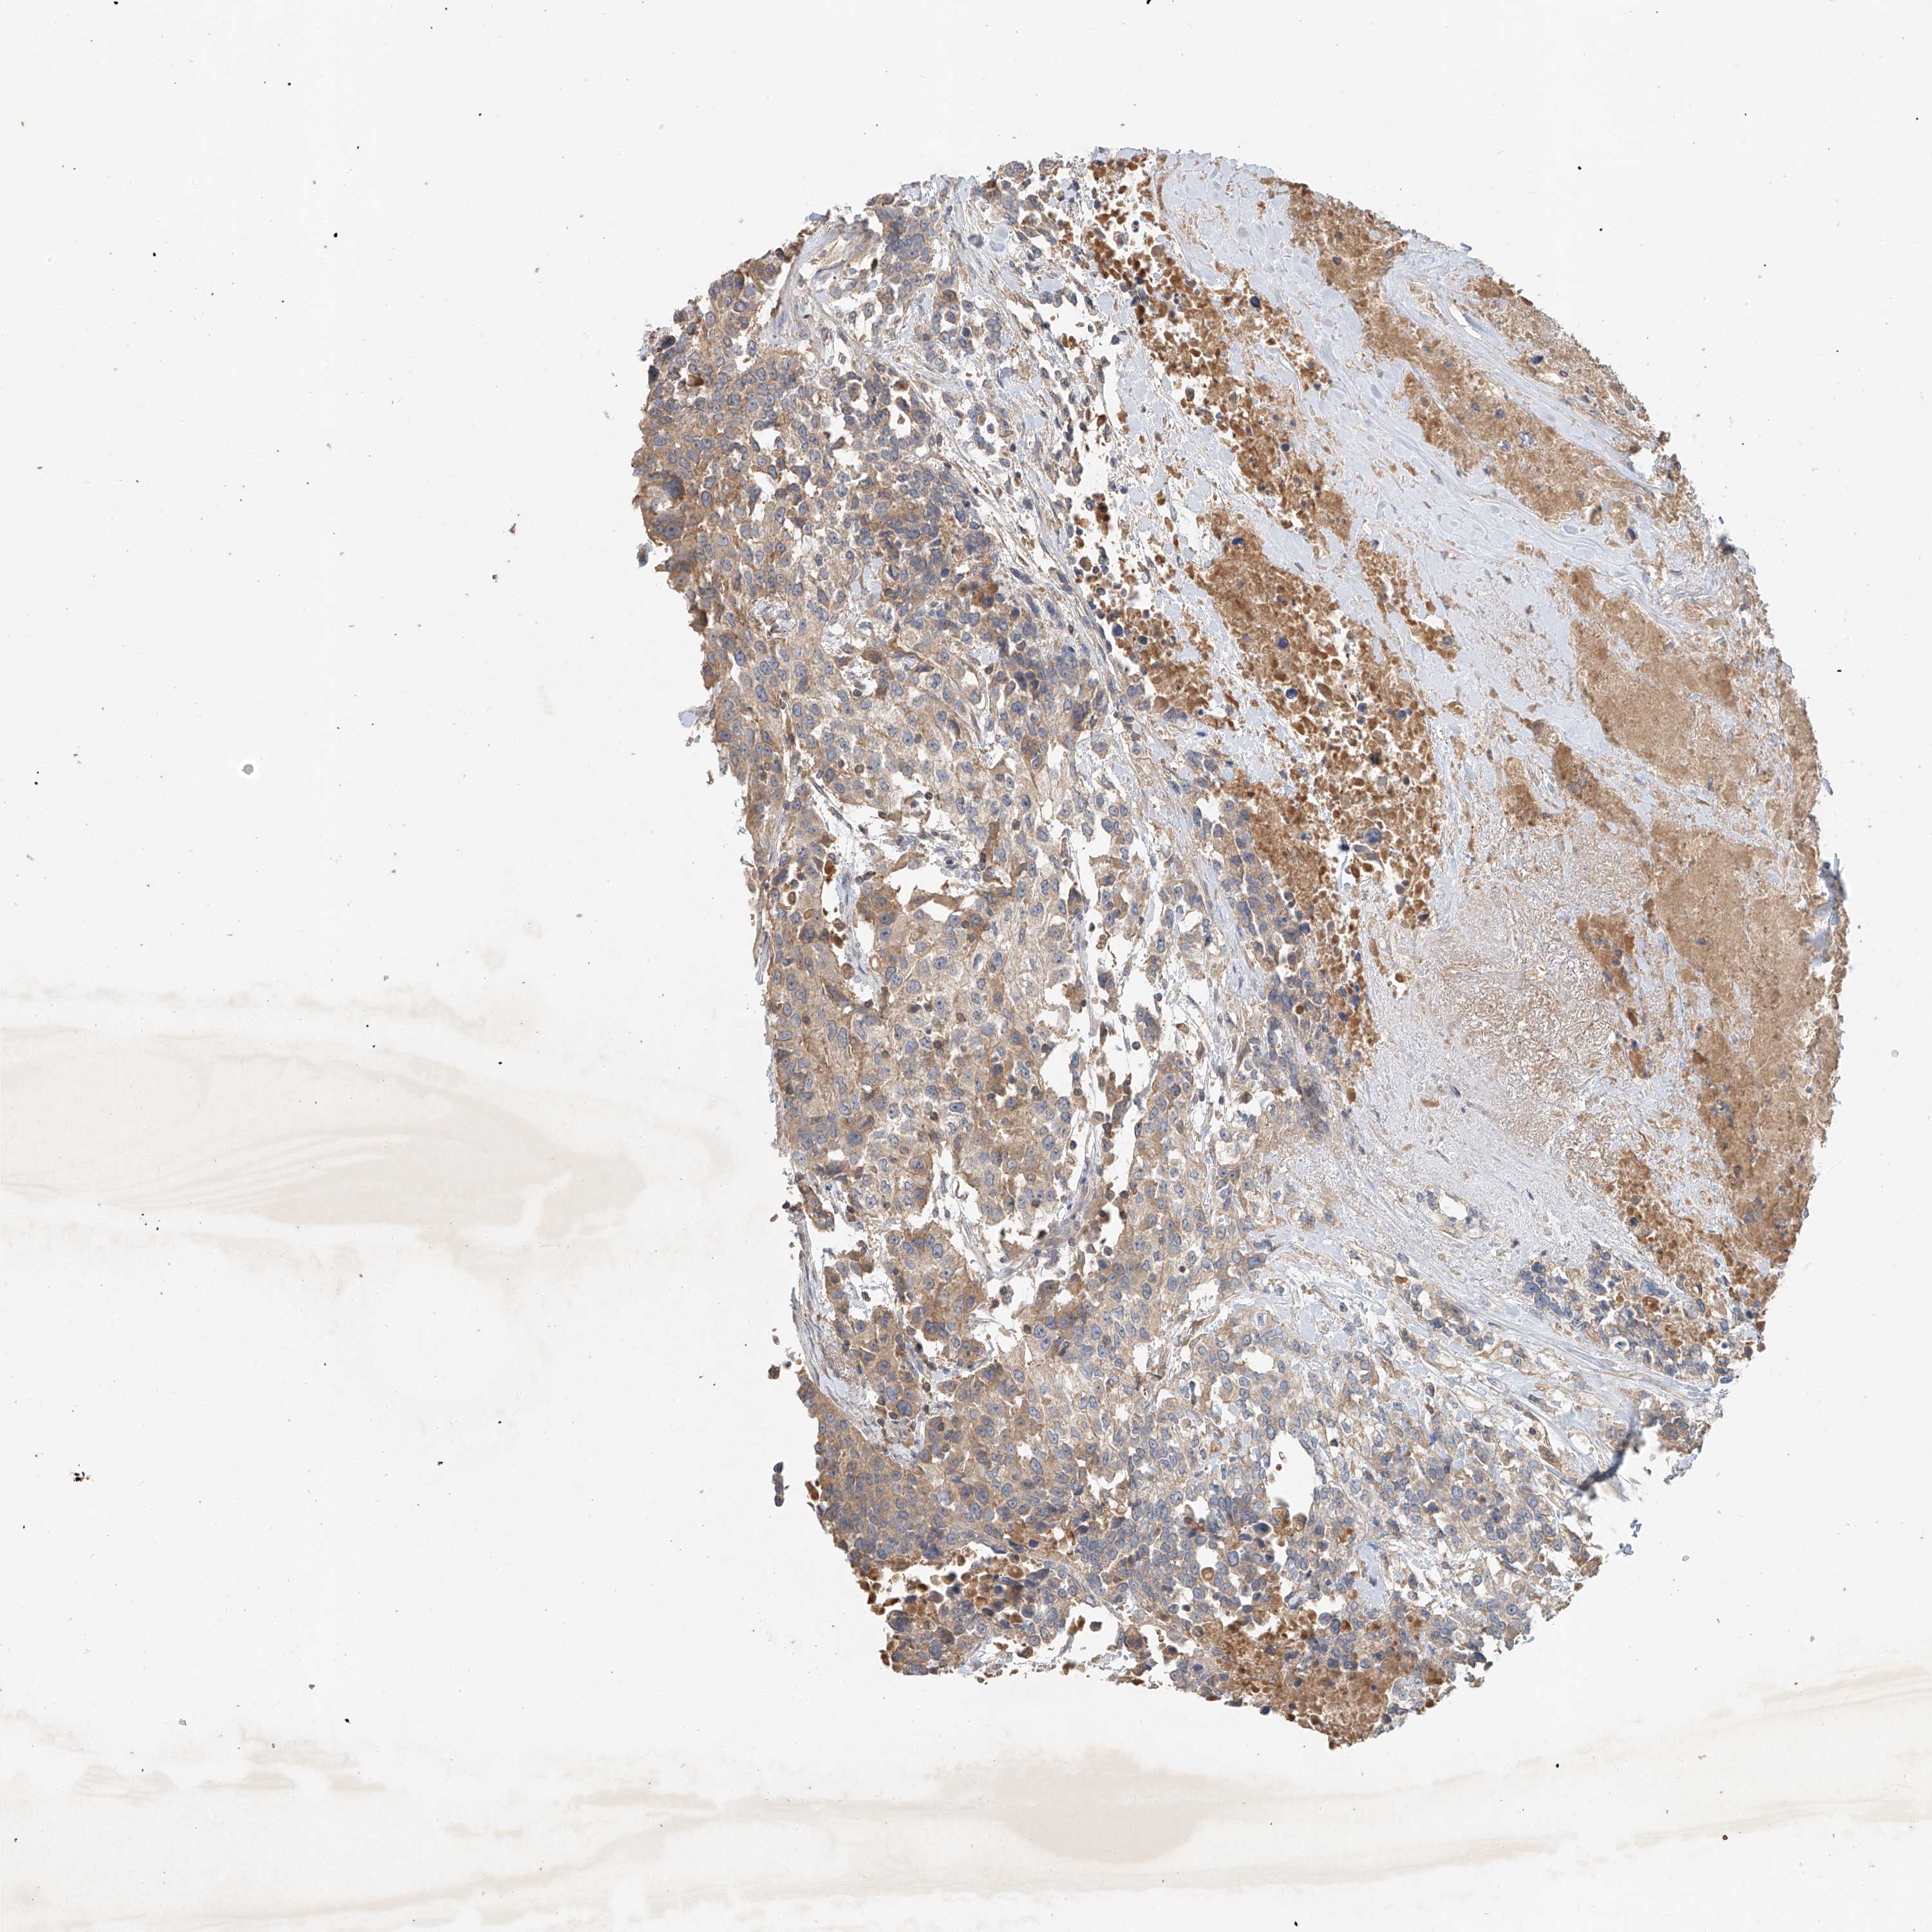

UROTHELIAL CANCER - Protein expressioni

A mouse-over function shows sample information and annotation data. Click on an image to view it in a full screen mode. Samples can be filtered based on level of antibody staining by selecting one or several of the following categories: high, medium, low and not detected. The assay and annotation is described here.

Antibody stainingi

Antibody staining in the annotated cell types in the current human tissue is reported as not detected, low, medium, or high, based on conventional immunohistochemistry profiling in selected tissues. This score is based on the combination of the staining intensity and fraction of stained cells.

Each image is clickable and will lead to virtual microscopy that enables deeper exploration of all samples and also displays staining intensity scores, fraction scores and subcellular localization as well as patient and tissue information for each sample.

Antibody HPA034627

Staining

High

Medium

Low

Not detected

Intensity

Strong

Moderate

Weak

Negative

Quantity

>75%

75%-25%

<25%

None

Location

Nuclear

Cytoplasmic/membranous

Cytoplasmic/membranous,nuclear

Urothelial carcinoma, Low grade

Urothelial carcinoma, High grade